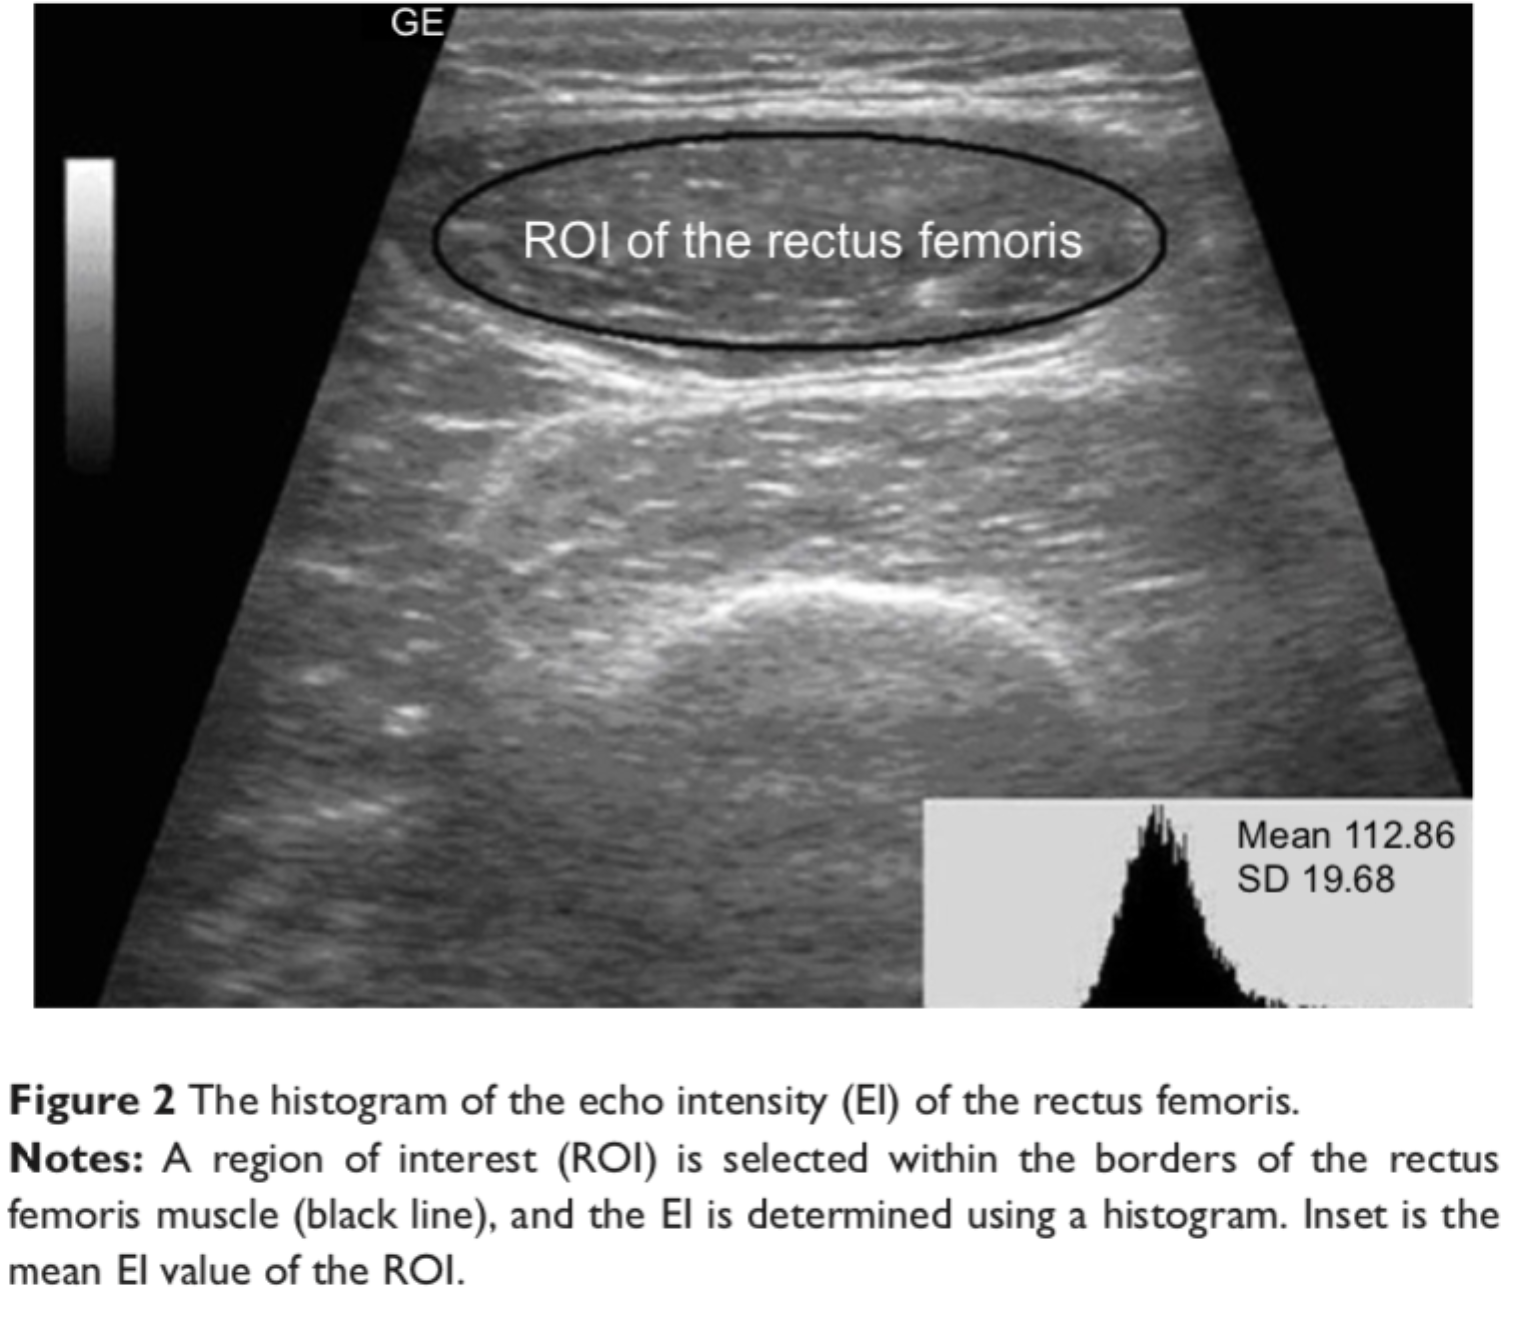

叶熊博士潜心于教学和自然科学研究,不忘初心、默默耕耘。分别主持厅局级和省部级项目各1项,校级项目3项,总资助经费30万元,发表第一作者SCI论文3篇,累计影响因子11.133分。于2017年10月,在《Int J Chron Obstruct Pulmon Dis》杂志(IF:3.355)发表题为“Echo intensity of the rectus femoris in stable COPD patients”的研究论文1篇,该研究探索了一种超声图像回声强度定量方法,用于评估慢性阻塞性肺病患者股四头肌功能,有助于早期诊断慢性阻塞性肺病患者的骨骼肌功能失调;于2021年5月,在《Frontiers in Medicine》杂志(IF:5.091)发表题为“A Novel Normalized Cross-Correlation Speckle-Tracking Ultrasound Algorithm for the Evaluation of Diaphragm Deformation”的研究论文1篇,该研究首次把互相关归一算法用于膈肌超声斑点追踪,为研究膈肌动力学提供了一种创新性的方法。该成果是叶熊老师和清华老员工物工程系罗建文研究员团队合作的阶段性成果